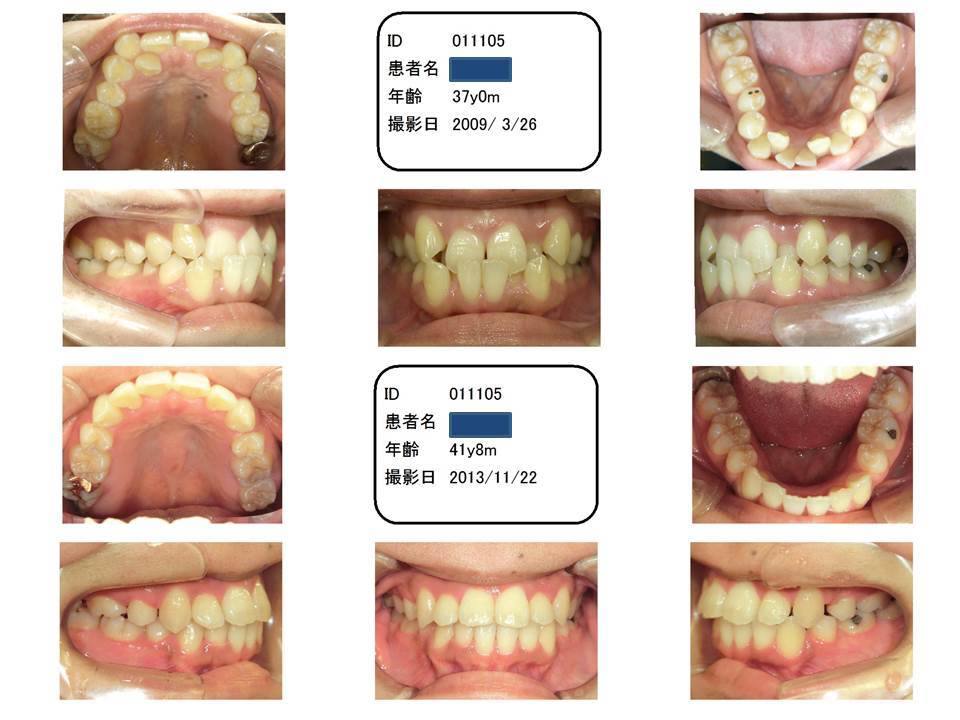

受け口もある八重歯

この症例は、前歯が上下でジグザグになっています。

まず、下の前歯、その後ろに上の前歯、そして、下、上と続きます。

ということで、上の前歯が下の前歯を乗り越えるのに非常に苦労した症例です。そのため、治療期間が長くなりました。